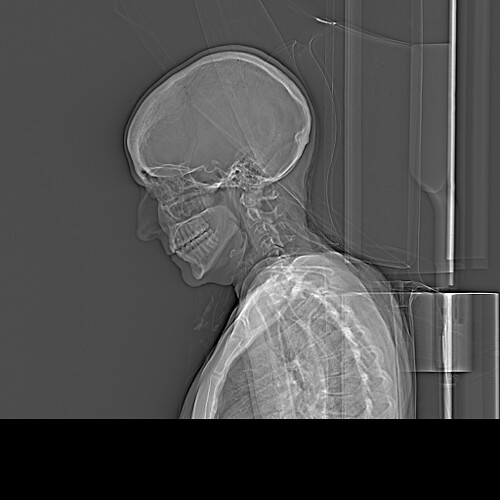

Thank you for welcoming me into this group. I am new. I have been in hell since 2023, but before that have had bizarre and bad symptoms since around 2016, but really bad since 2018: severe migraines and pain shooting into the left side of my face (one of the worst symptoms), neck pain, ears blocked and ringing in my ears, sinuses blocked and pressure, dizziness and vertigo, severe neck cracking, brain fog, vision problems (the other worst symptom) on the left side, pain around the ear, jaw pain and bite problems (teeth don’t touch at all in back suddenly for no reason), occasional numbness in the back of my head, trouble talking and fatigue talking (bad symptom), tongue fatigue and problems, throat issues, painful spot behind left upper molar area, and more. It’s been a hellscape. I do not know what is going on but my sister read about Eagle Syndrome, and then she and I both uploaded my X-rays into AI and it said they were elongated and prominent. If it’s not this, it’s my cervical spine, but my cervical spine MRI only shows “mild degenerative changes.” I am 57 years old and female. Most people my age would have mild degenerative changes. I have been to several doctors for the neck issue and most have said my cervical spine could not be responsible. But, one new one I saw recently said my spine IS causing my “headaches” but he did not say what part of my spine is responsible or how it is causing all of this. He just said “the pain is coming from your neck.” He wants to put Botox into my SCM muscles and if that does not work, do facet joint injections at C5, C6, and C7. I am not necessarily opposed to this, but my question is: Why? What evidence is this being based upon? The treatment seems to be just a shot in the dark. How long do I go on taking all kind of meds (been there, done that, to no effect) and letting all kind of docs do all kinds of scary procedures on me without knowing what is wrong?

Anyway I have two lateral X-rays taken in 2023 and 2024 when I went to the ER with severe pain and they ruled out stroke. Is anyone available to read them?